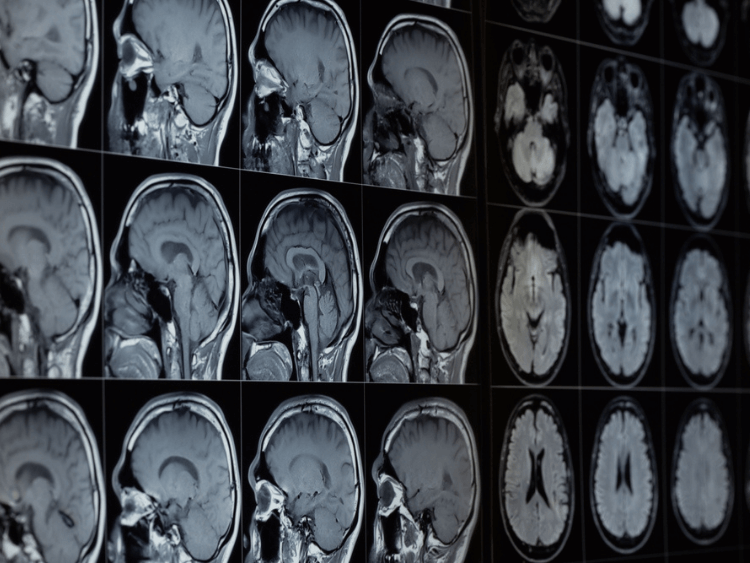

Manyetik Rezonans Görüntüleme (MRG): Beyin ve omuriliğin ayrıntılı görüntülerini sağlayarak anormallikleri tespit eder.